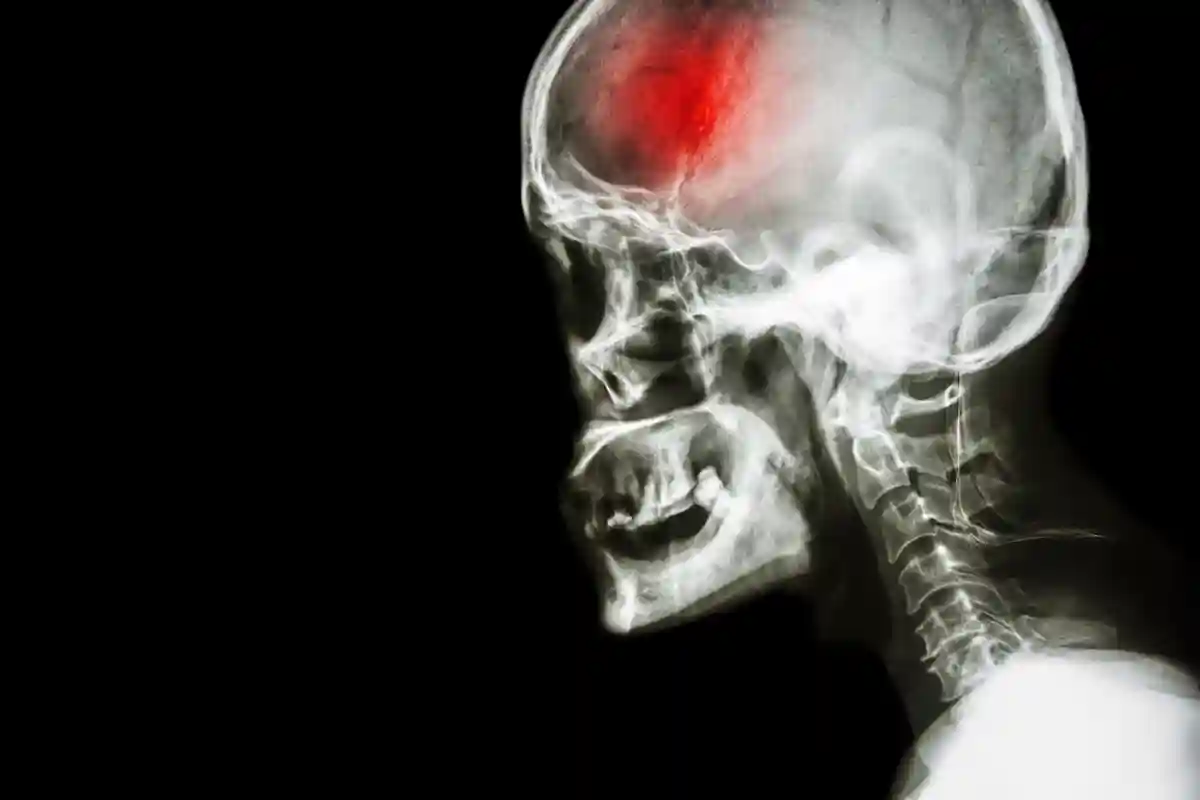

Kas yra Insultas ir Kodėl Jis Pavojingas?

Insultas, arba smegenų infarktas, yra ūmus galvos smegenų pažeidimas, kurį sukelia staiga nutrūkusi kraujotaka tam tikroje smegenų dalyje arba kraujo išsiliejimas į smegenis. Tai yra viena pavojingiausių būklių, galinti negrįžtamai pakeisti žmogaus gyvenimą, sukelti nuolatinę negalią ar net mirtį. Nors dažniausiai insultas ištinka vyresnio amžiaus žmones, retais atvejais jis gali pasireikšti ir kūdikiams ar jauniems asmenims dėl įvairių priežasčių, pavyzdžiui, paveldimų ligų ar kraujagyslių pakitimų. Suaugusiųjų insulto priežastys dažniausiai susijusios su gyvenimo būdu ir įgytomis ligomis. Insulto padariniai gali būti itin sunkūs, todėl būtina žinoti jo požymius ir nedelsiant kreiptis medicininės pagalbos.

Du Insulto Tipai: Kuo Jie Skiriasi?

Medicina išskiria du pagrindinius insulto tipus, kurie skiriasi savo atsiradimo mechanizmu:

Išeminis insultas (smegenų infarktas)

Tai yra dažniausiai pasitaikantis insulto tipas, sudarantis apie 75–80 procentų visų atvejų. Išeminis insultas ištinka, kai smegenų kraujagyslę užkemša trombas (kraujo krešulys) arba embolas (į smegenis atkeliavęs svetimkūnis, pavyzdžiui, dalis trombo, susiformavusio kitose kūno vietose). Trombai dažniausiai susidaro tose kraujagyslių vietose, kurios pažeistos aterosklerozės, o aterosklerozinės plokštelės susiaurina kraujagyslės skersmenį. Embolai, priešingai, susidaro ne smegenyse, bet pasiekę siauras smegenų kraujagysles, jose įstringa. Išeminis insultas dažniausiai ištinka vyresnius nei 55 metų asmenis, neretai – miego metu. Kartais jam gali būti būdingas galvos skausmas, ypač po sunkaus fizinio darbo.

Hemoraginis insultas

Šis insulto tipas yra retesnis, tačiau dažnai sunkesnis. Hemoraginis insultas įvyksta, kai smegenų kraujagyslė plyšta ir kraujas išsilieja į aplinkinius smegenų audinius. Šio tipo insultas dažniausiai pasireiškia dienos metu, neretai po didelio fizinio krūvio ar stipraus streso. Pacientas gali staiga prarasti sąmonę ir patekti į komos būseną, kuri gali trukti nuo kelių valandų iki kelių parų. Sąmonei aiškėjant, dažnai pasireiškia stiprus galvos skausmas, svaigimas, kvėpavimo sutrikimai, traukuliai ir vienos kūno pusės paralyžius.